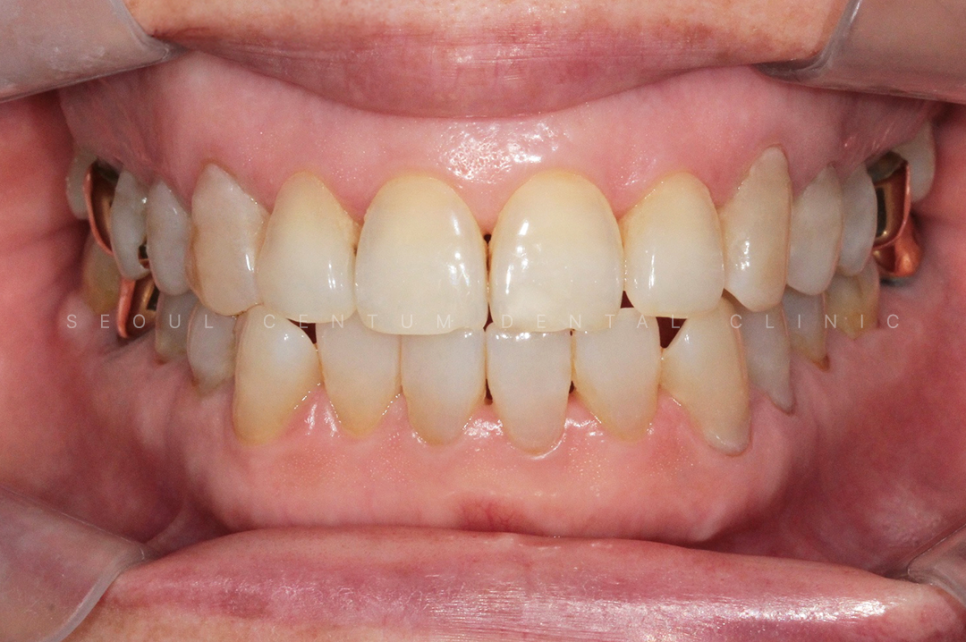

Previous image Next image

확실히 하고 안하고 심미적으로도

차이가 큰 편이기 때문에

하고나서 환자 본인도 만족도가 매우 높은

부분이라고 할 수 있겠습니다.

레진으로 깔끔하게 치료를 하니

심미적으로도 한결 보기 좋고

치아도 앞으로 보호가 되는 부분이라

안심하고 식사를 하실수가 있겠는데요.

이렇듯 하루에 문제가 해결되는

간단한 치료이며 외관적으로도

만족도가 굉장히 높은 부분입니다.